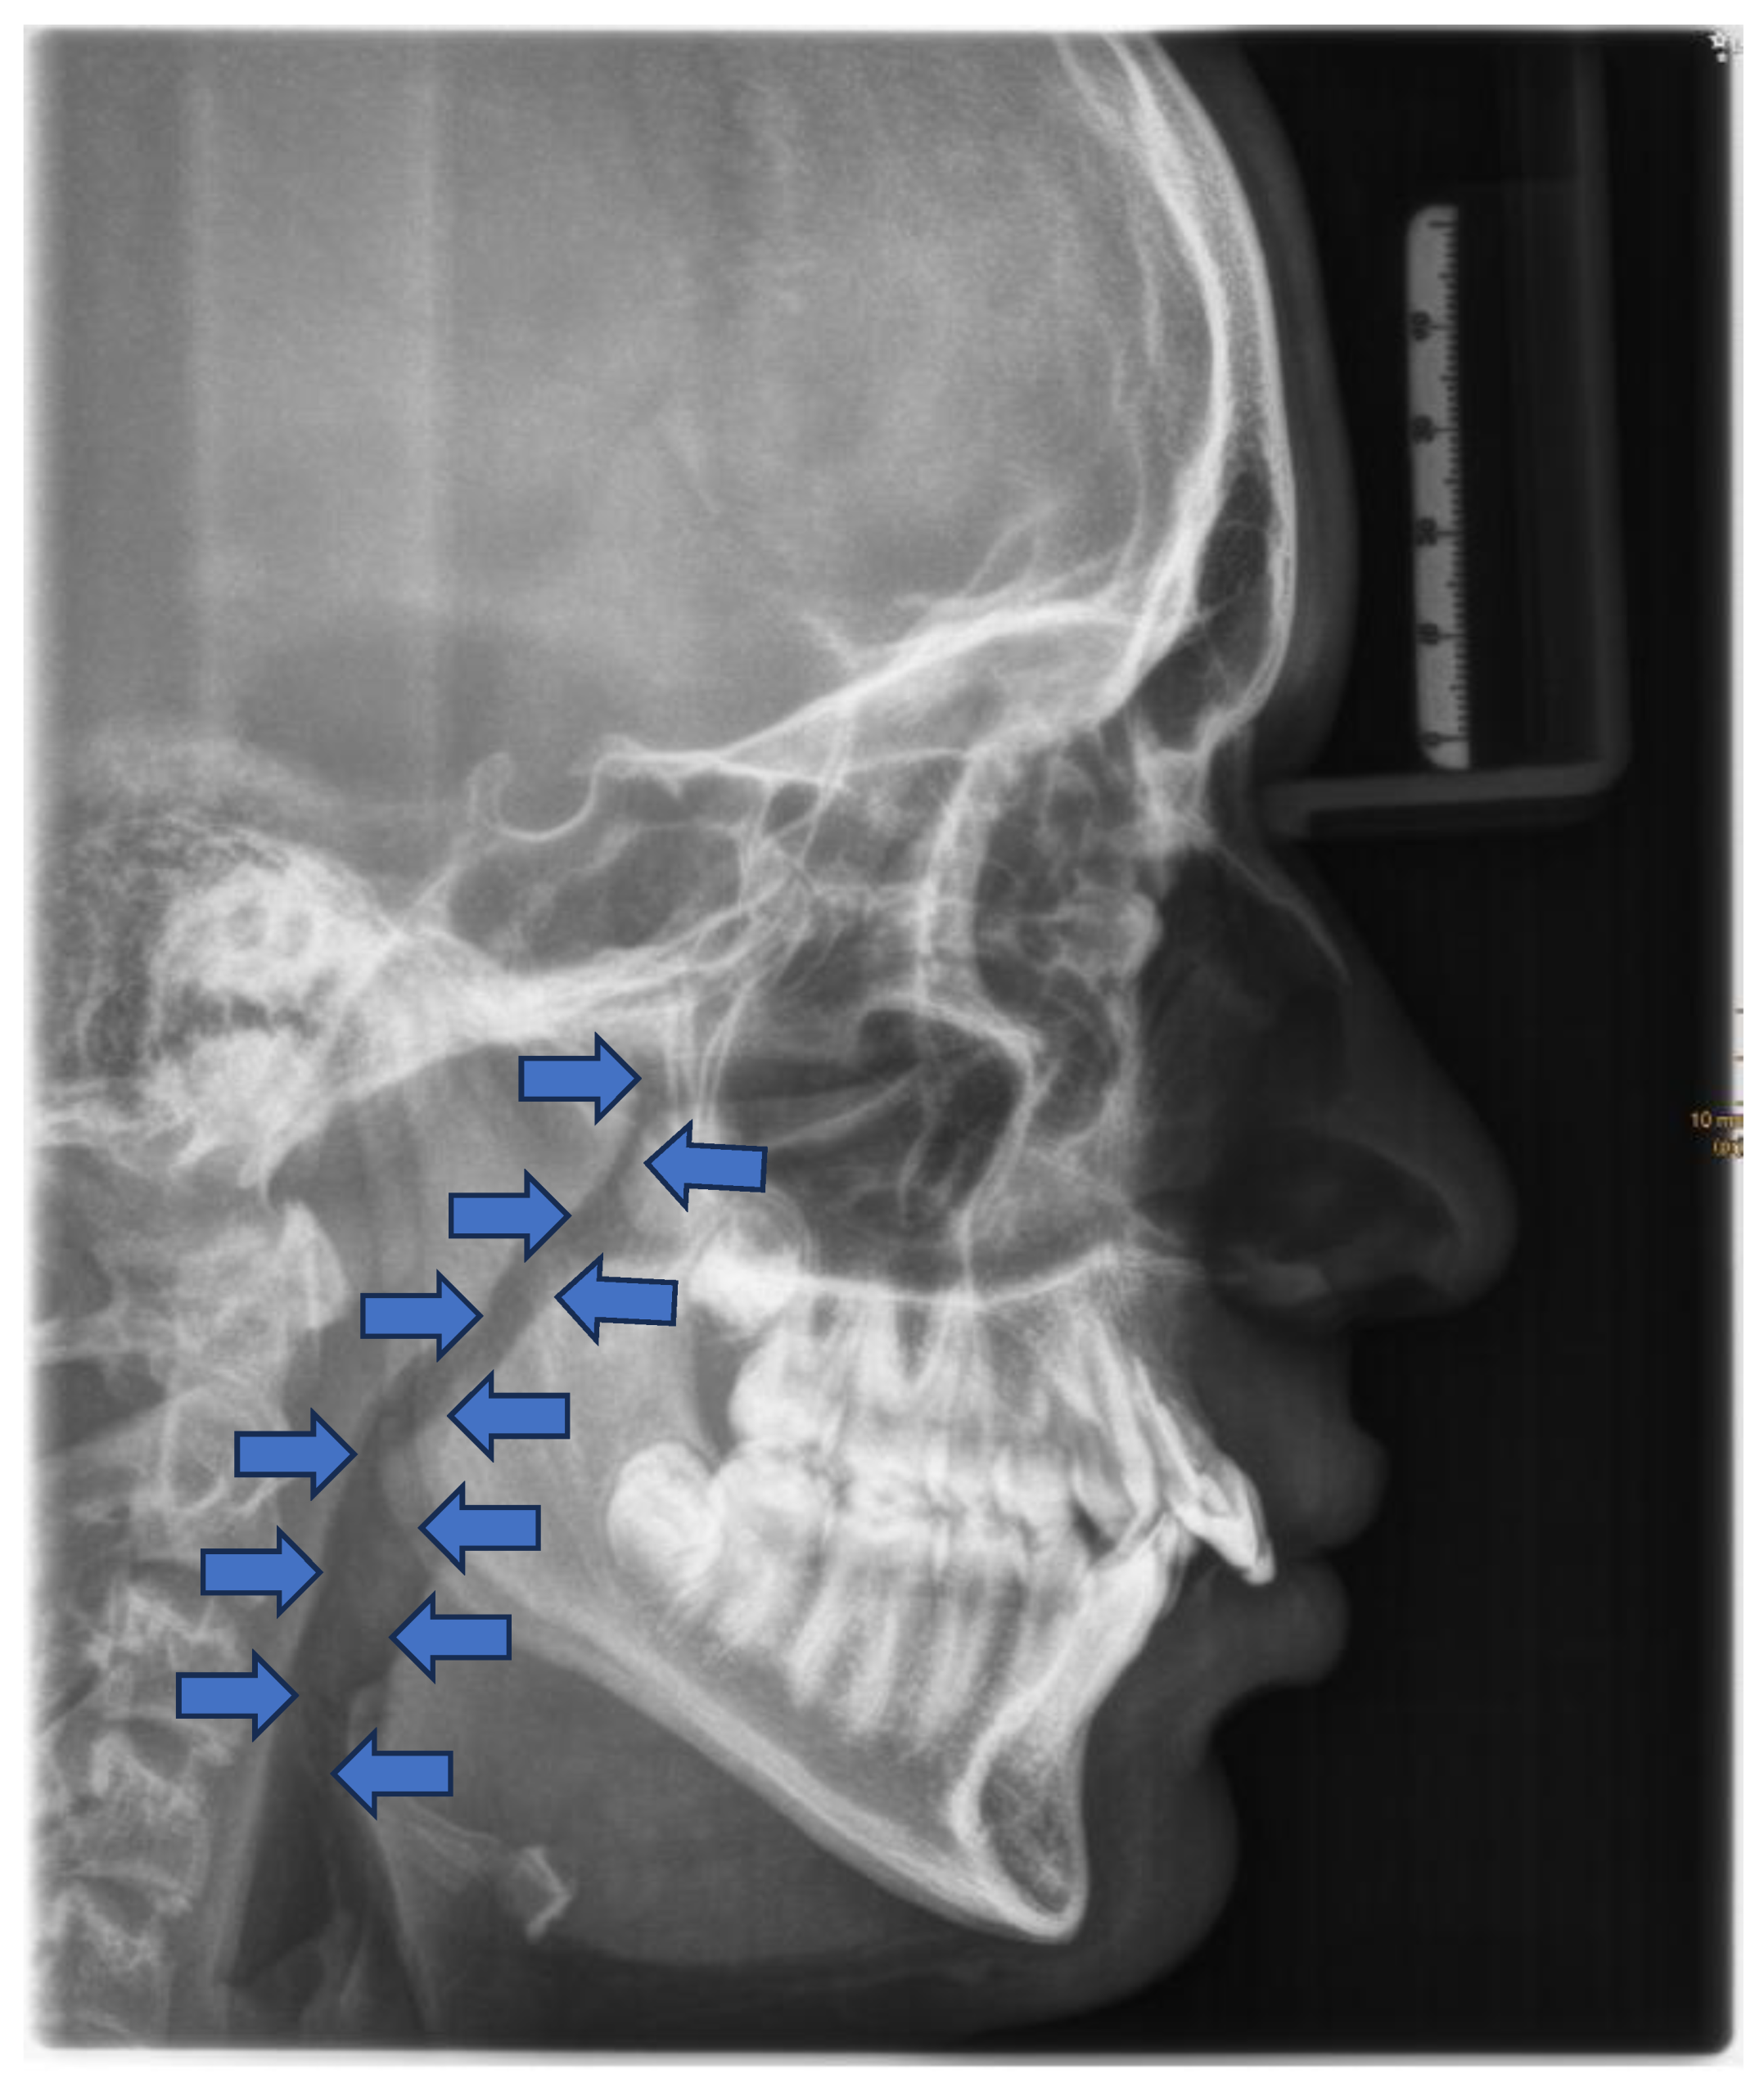

Cephalometric evaluations of patients with OSA have revealed several skeletal (a) and soft tissue (b) morphological differences compared to the normative values (Table 1) [67,68].

The consequences of these aberrations result in reduced size of the bony pharynx and a hyperdivergent facial pattern characterized by a larger anterior facial height. A bimaxillary retrognathic pattern, which is more pronounced in the mandible, further decreased facial depth and contributed to a narrowed posterior airway space [69]. Together, these structural changes significantly reduce upper airway volume, thereby predisposing affected individuals to OSA. (Figure 3)

These patients often exhibit “adenoid facies” characteristics and present with dark circles around the eyes, flattened cheekbones, dry lips, an open-mouth posture, a lowered mandibular posture, a low tongue position, labial incompetence, underdeveloped nasal bones, pronounced nasolabial furrows, which collectively complete the typical appearance [49,55,56,57]. They often present a convex profile due to a retrognathic mandible (Figure 4) and an increased mandibular angle. The lower facial third is frequently longer than the average (long-face, dolichofacial morphology) [55]. (Table 2). Additionally, they exhibit an altered head position resulting from hyperextension of the cervical spine and an overall reduction in orofacial muscle tonicity.

Malocclusion is highly prevalent in children with OSA. They often present posterior crossbites in addition to lateral functional shifts due to a narrow maxilla [70,71,72]. Regarding the palatal vault, it is higher and narrower than in not affected children [73]. This is related to the altered equilibrium between the tongue and cheeks [58]. In addition, an anterior open bite (reduced overbite) and sometimes a deep bite (increased overbite), an increased overjet due to a retrognathic mandible, protruded upper incisors, and crowding in the maxilla and the mandible are constant findings [55,74,75]. (Figure 5 and Table 2)